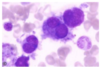

Promegakaryocyte

Promegakaryocyte

Proerythroblast

Proerythroblast

Reticulocytes